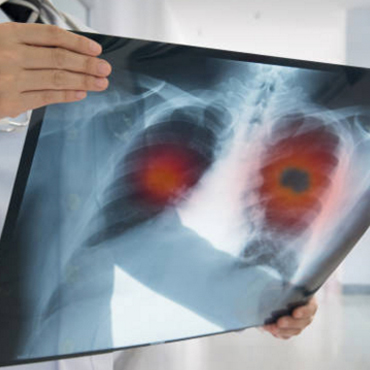

CÁNCER PULMONAR

El cáncer pulmonar es la principal causa de muerte por cáncer a nivel mundial, pero su diagnóstico oportuno y tratamiento adecuado puede modificar esto.